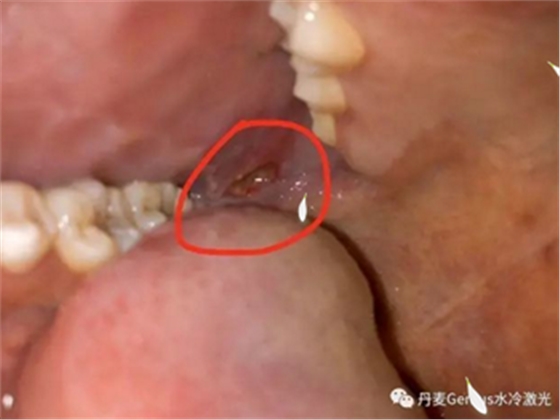

淺表黏膜膿腫切開(kāi)引流

在常規(guī)消毒后,涂抹本品,再行切割。在更換藥物時(shí),也可以涂抹